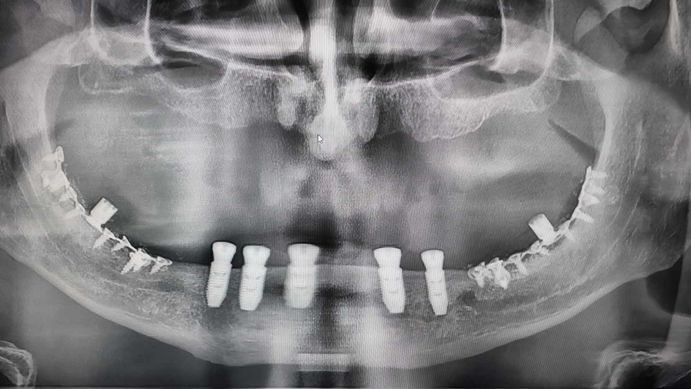

Réhabilitation mandibulaire sur implants

Le patient présente un cas spécial d'absence congénitale de plusieurs dents, qu'il n'a jamais eu depuis la naissance. Des implants ont été posés sur la mandibule et des implants seront également réalisés sur le maxillaire à l'avenir. Nous partagerons les photos ultérieurement.